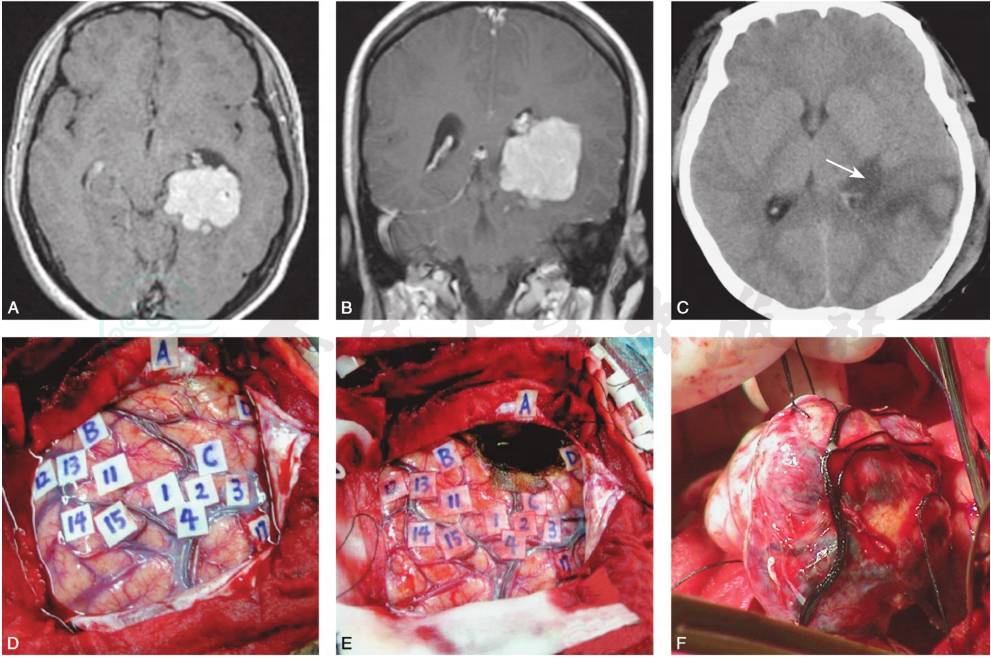

侧脑室内脑膜瘤的手术入路较多,如枕叶入路、顶叶入路、颞中回入路、颞枕入路和纵裂入路等,各有优缺点。侧脑室三角区脑膜瘤常采用顶上小叶(顶间沟)入路,位于侧脑室颞角者可采用颞中回入路,但该入路易造成视放射损伤,优势半球手术可导致语言功能障碍,术前可行功能MRI检查,术中可在唤醒麻醉下行语言区定位,以确定皮层造瘘口(图3)。侧脑室前部的肿瘤可采用纵裂胼胝体入路。无论采用哪种入路均应力求在非功能区切开。侧脑室内较小的脑膜瘤一般边界比较清楚,与周围脑组织无粘连,可切断其供血动脉及脉络丛后将肿瘤整块取出。对于较大的肿瘤尤其是肿瘤与脑室内壁粘连紧密时,不可强行分离,应先行包膜内分块大部切除肿瘤,在显微镜下仔细分离和切除剩余的肿瘤组织。术中应注意利用棉片保护室间孔,防止血液流入对侧脑室及第三脑室,手术结束后应将脑室内的血块或血液冲洗干净。

图3术中唤醒麻醉下确定语言区,选择皮层造瘘口切除脑室内肿瘤